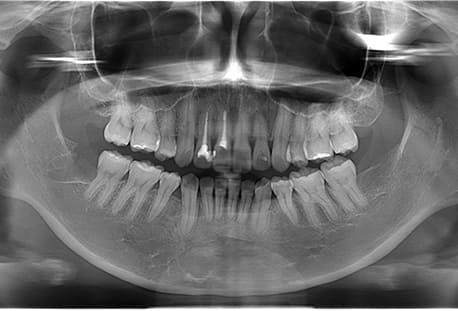

Case08

- 下顎の水平埋伏智歯2本

- 治療内容

- 下顎の水平埋伏智歯2本を抜歯したケースです。

<リスク・副作用>

手術後は痛み、腫れ、痺れなどの副作用が生じる場合があります。